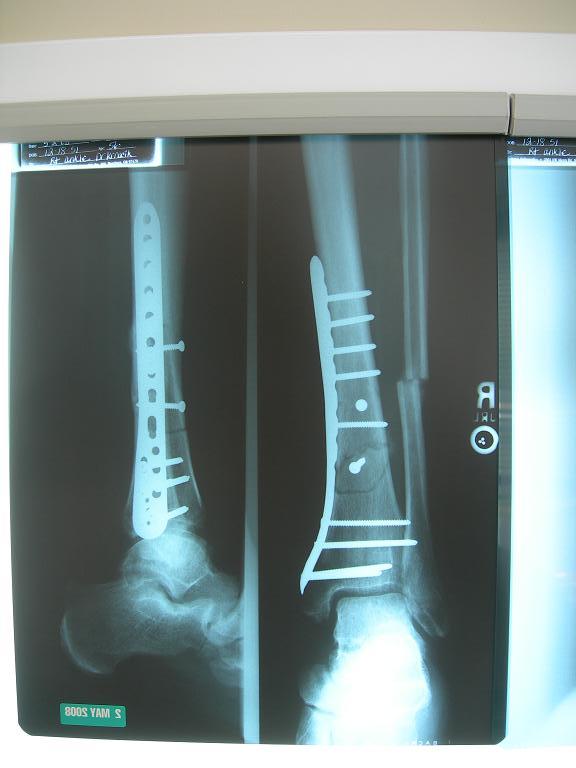

here's what it looked like after,, $60k

went in yesterday

now walking on it

with lots of swelling.

watch out for slednecks

DSCN2341.JPG |

| Damn blowhard, that's a lot of metal!

you'd think for the $

he'd snip off the ends sticking out ?

of my shin guard